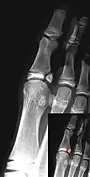

Salter–Harris II fracture of ring finger proximal phalanx.